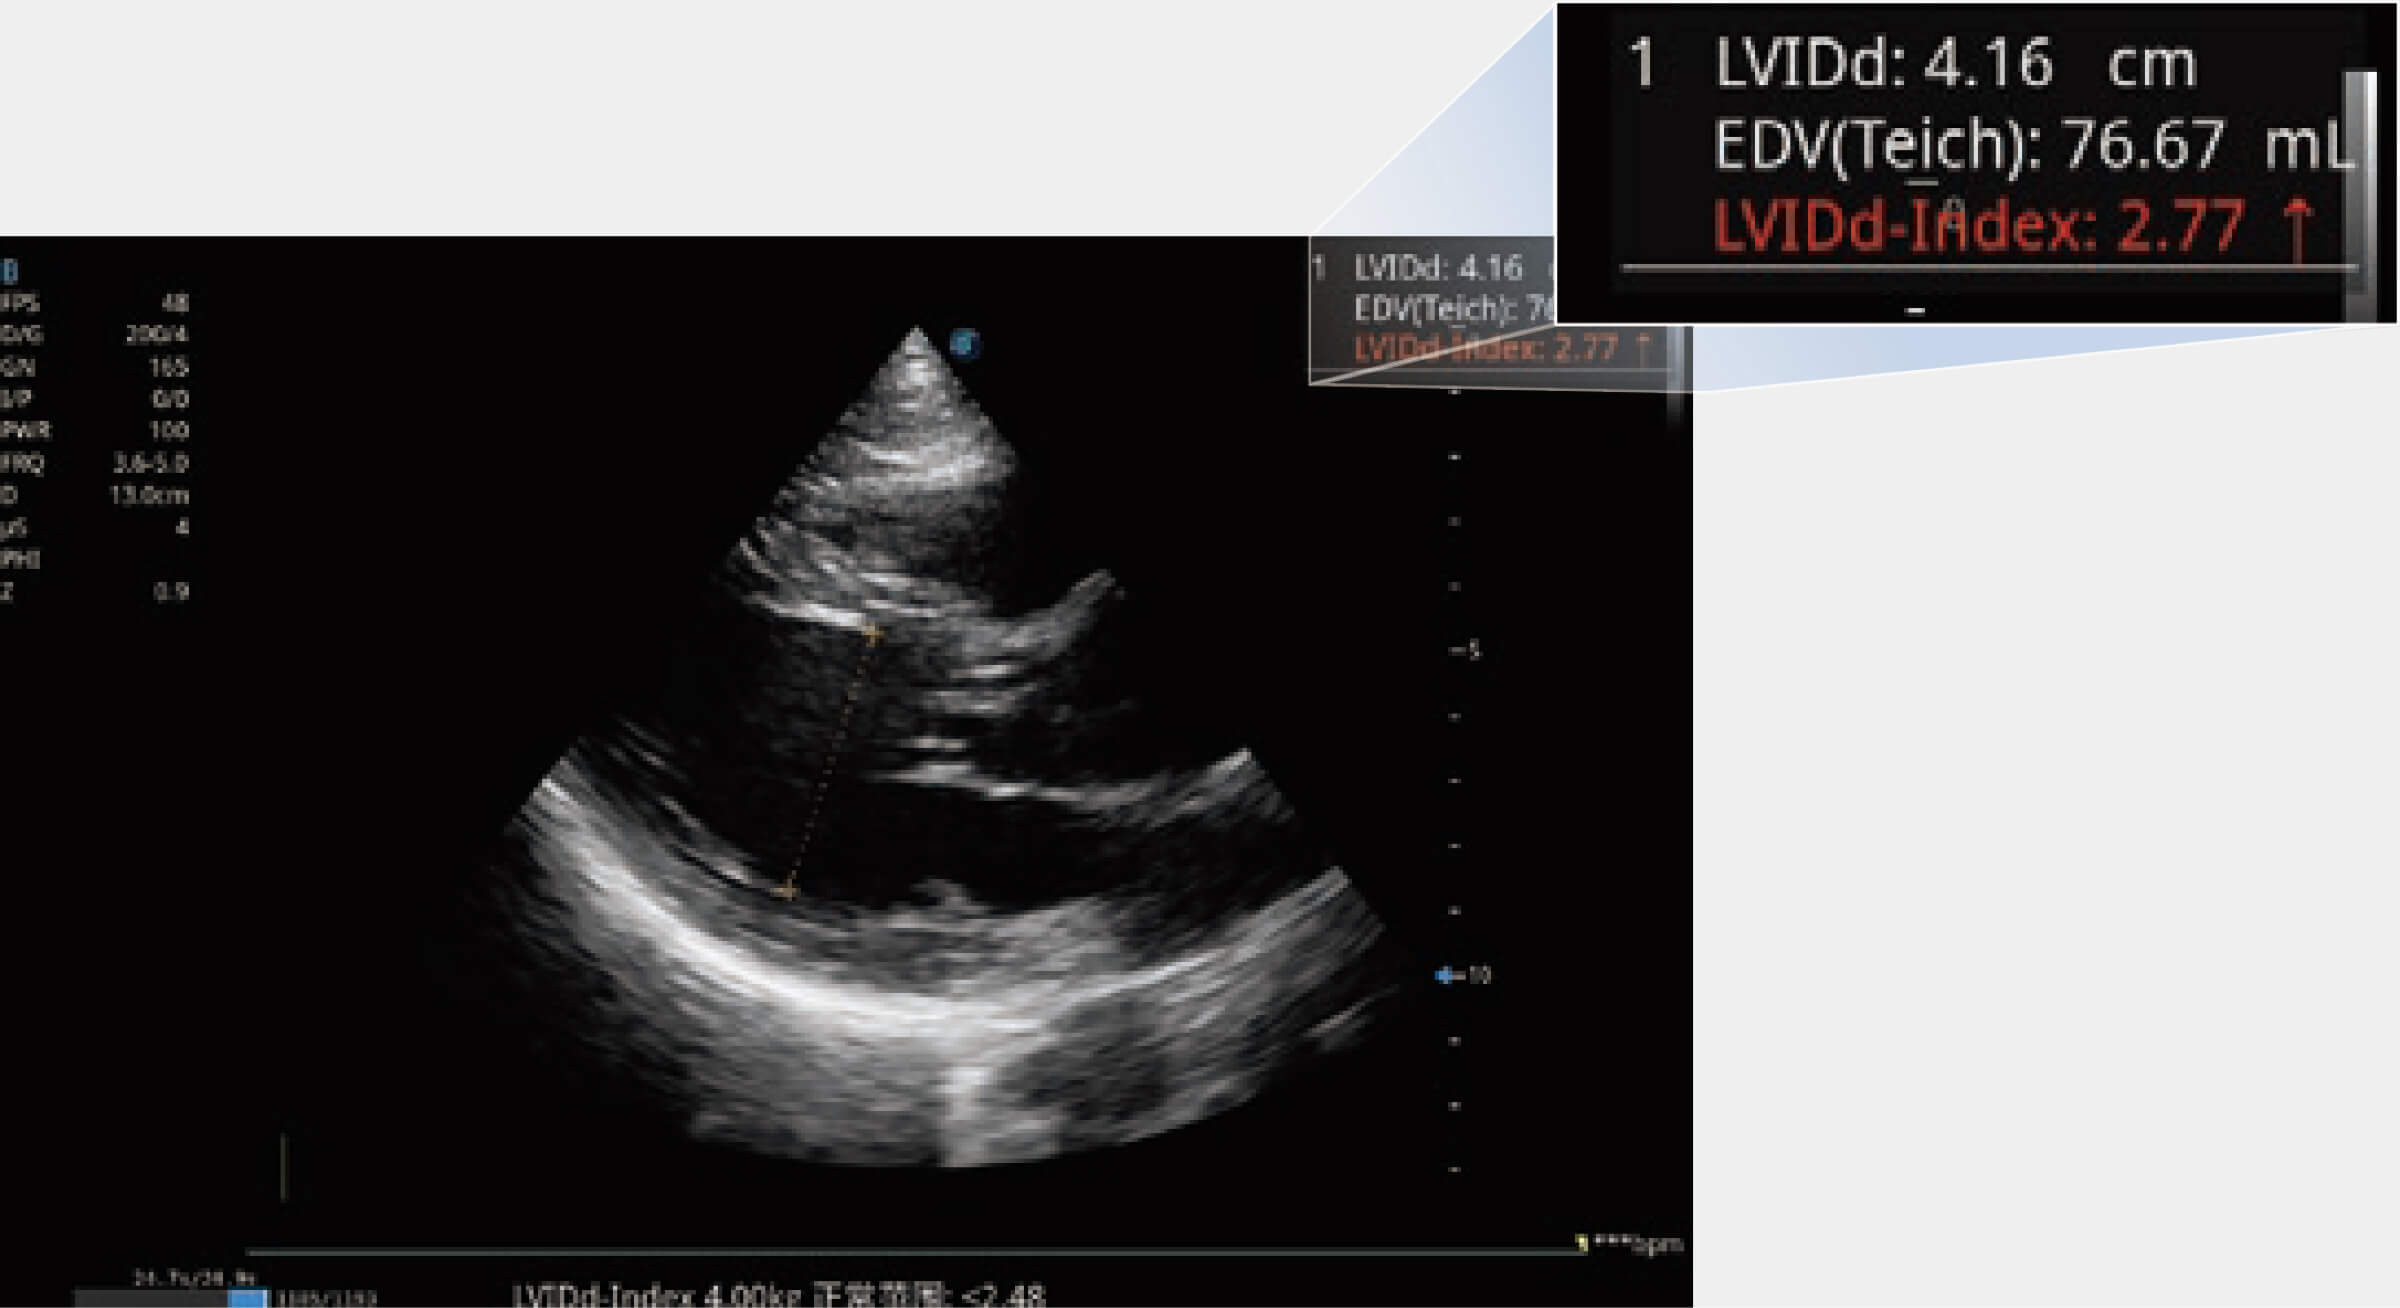

当心脏测量结果超出正常范围时,可实时预警提示动物医生,减少疾病漏诊概率。

ProPet 80 配备了丰富的心脏探头群、先进的成像技术和专业的心脏测量工具,可帮助动物医生为不同体型和生理结构的动物提供心脏和心肌功能的全面评估。

能够基于左心室壁追踪和辛普森法,自动计算射血分数,支持多个可移动点描迹,与手动测量相比,极大节省了动物医生的时间和精力。